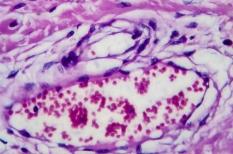

LES MALADIES

SYMPTÔMES